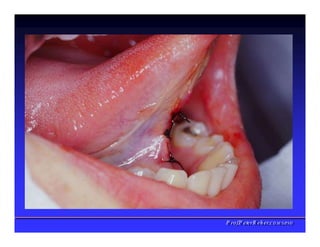

Assoalho da Boca